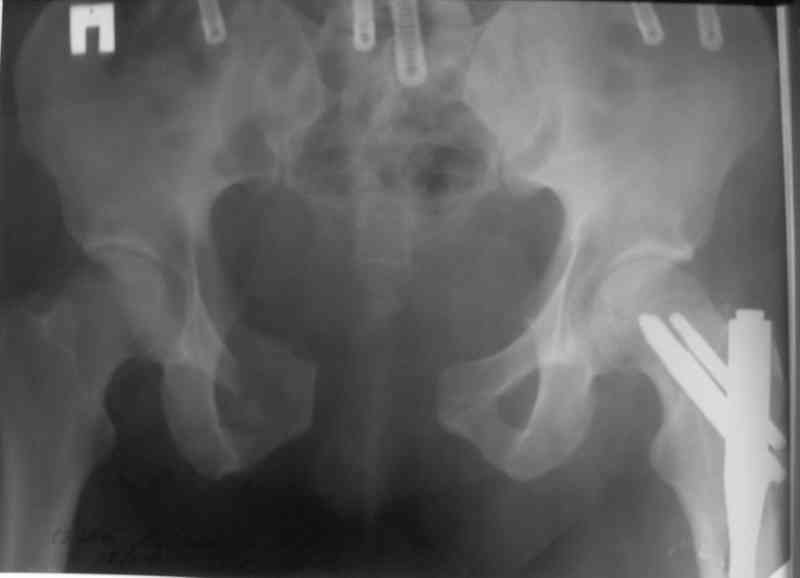

В приложении послеоперационные картинки.

Всего доброго,

Спасибо всем принявшим участие в обсуждении,

Чекашкин Е.И.